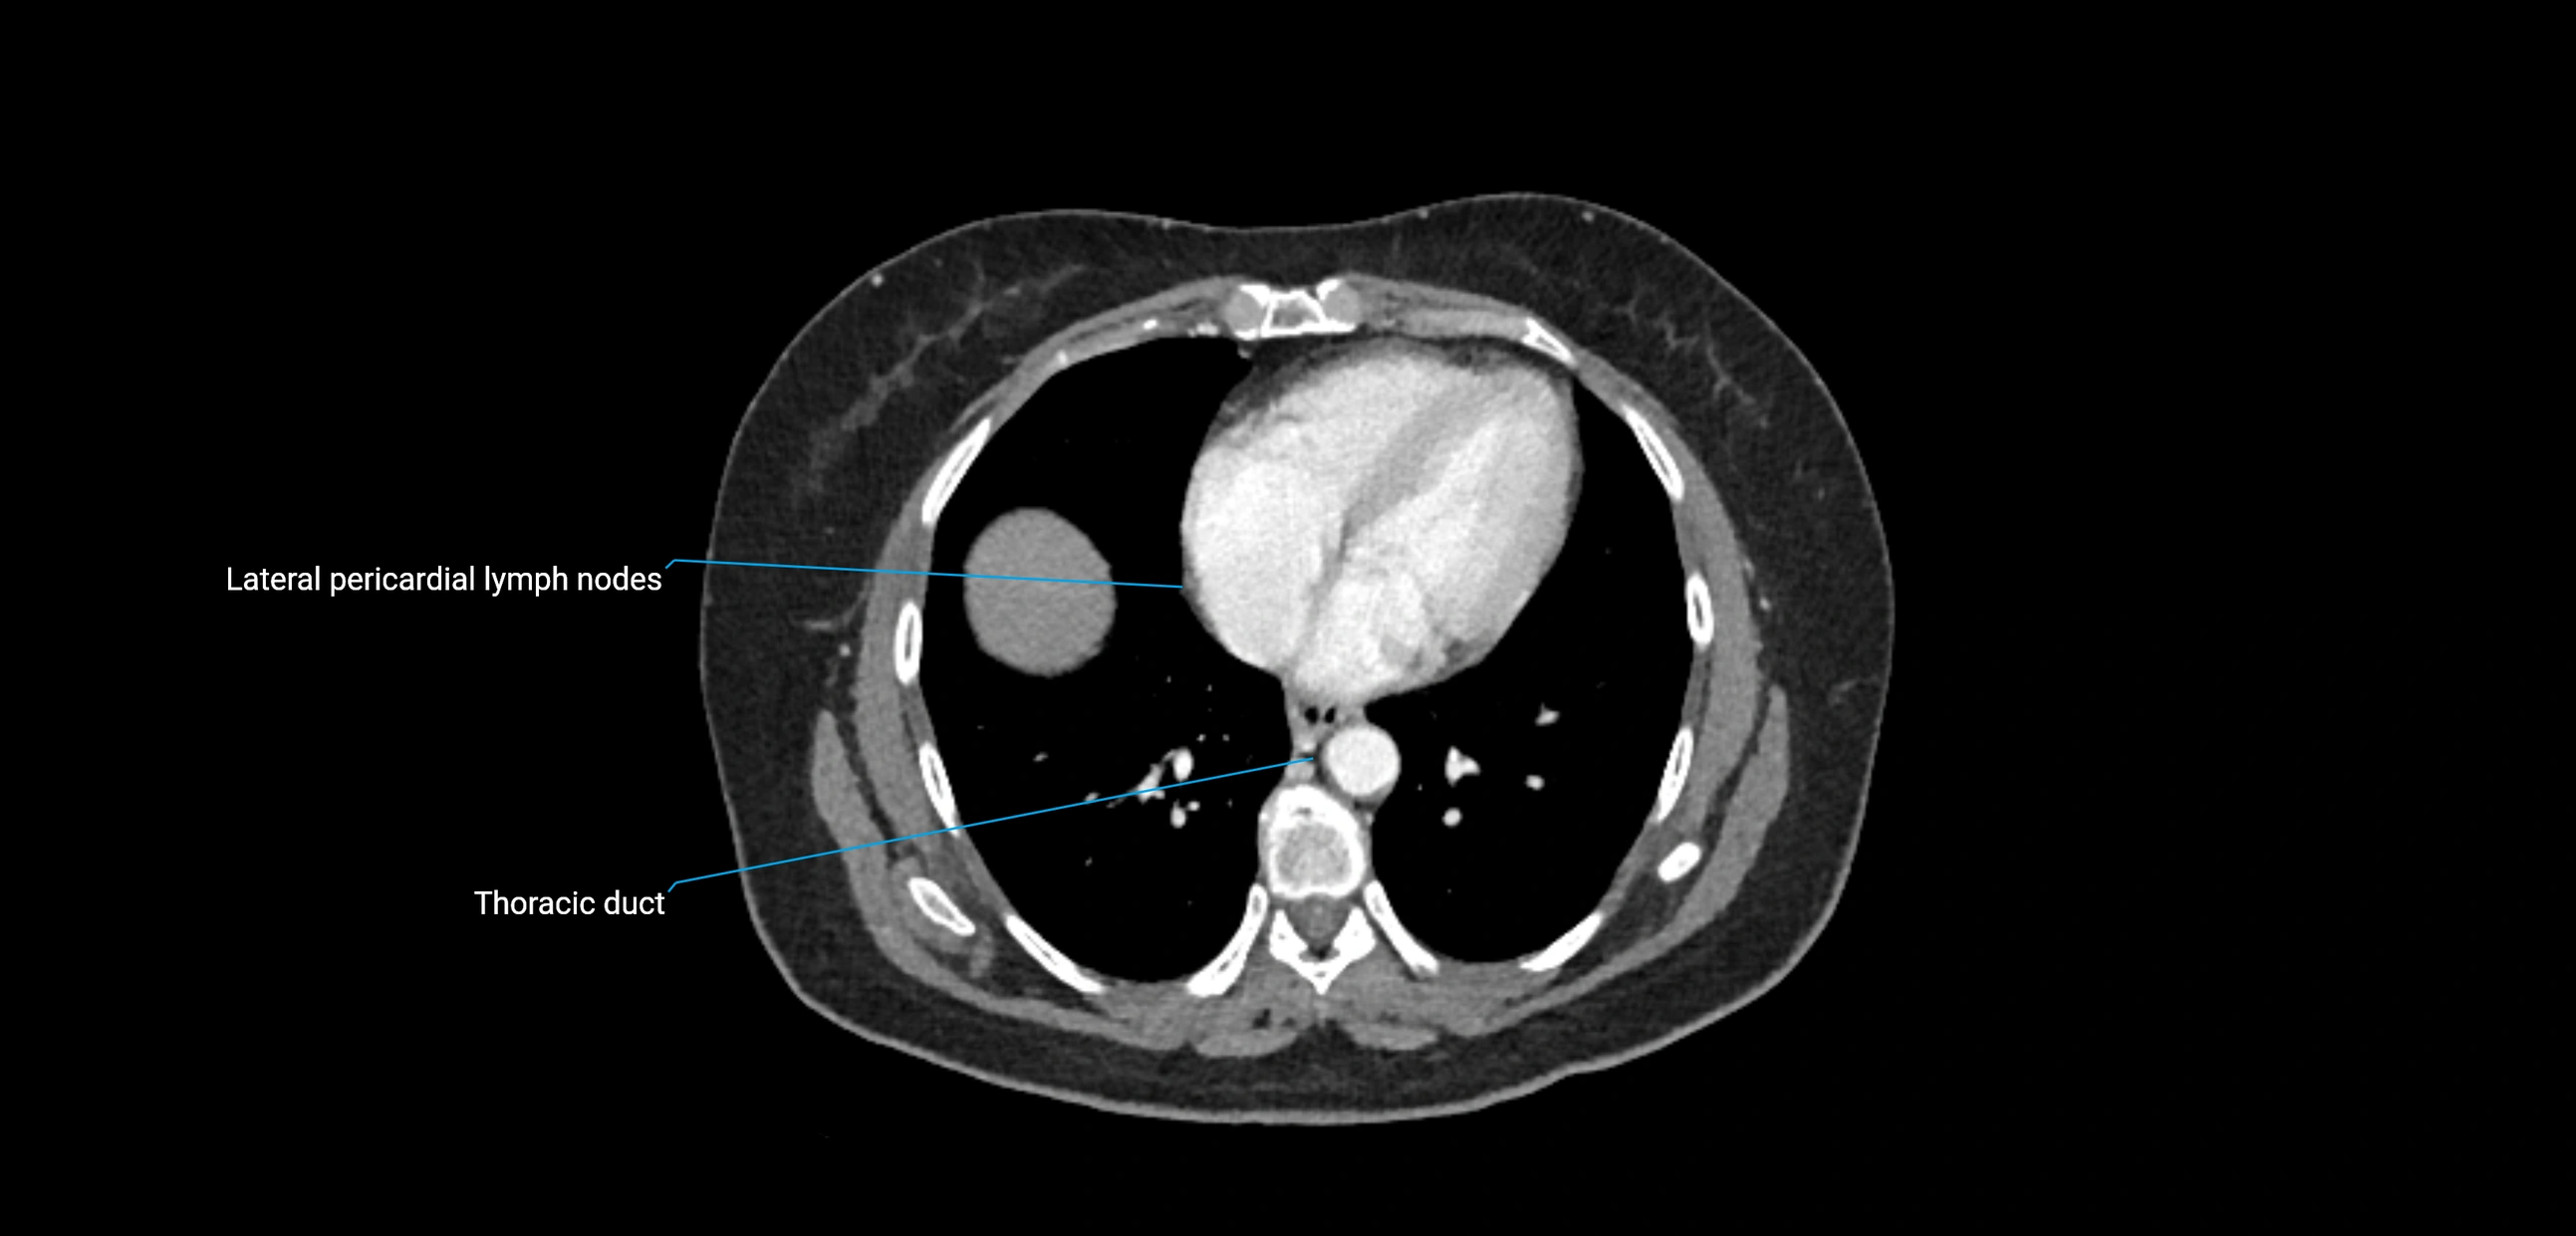

The lateral aortic lymph nodes (also called para-aortic lymph nodes) are a major group of retroperitoneal lymph nodes located along the abdominal aorta and its branches. They lie between the diaphragmatic crura superiorly and the bifurcation of the aorta at L4 inferiorly.

These nodes receive lymph from a wide range of abdominal and pelvic structures. Specifically, they drain lymph from the kidneys, suprarenal glands, gonads (testes/ovaries), uterus, uterine tubes, and pelvic organs, before converging into the lumbar lymphatic trunks, which terminate in the cisterna chyli → thoracic duct.

• Provide a major pathway to the cisterna chyli and thoracic duct

CT Venography (CTV):

• Demonstrates nodal encasement or compression of adjacent vessels (aorta, IVC, renal veins)

• Useful in staging testicular and ovarian malignancies

• Provides 3D reconstructions for retroperitoneal lymph node dissection planning